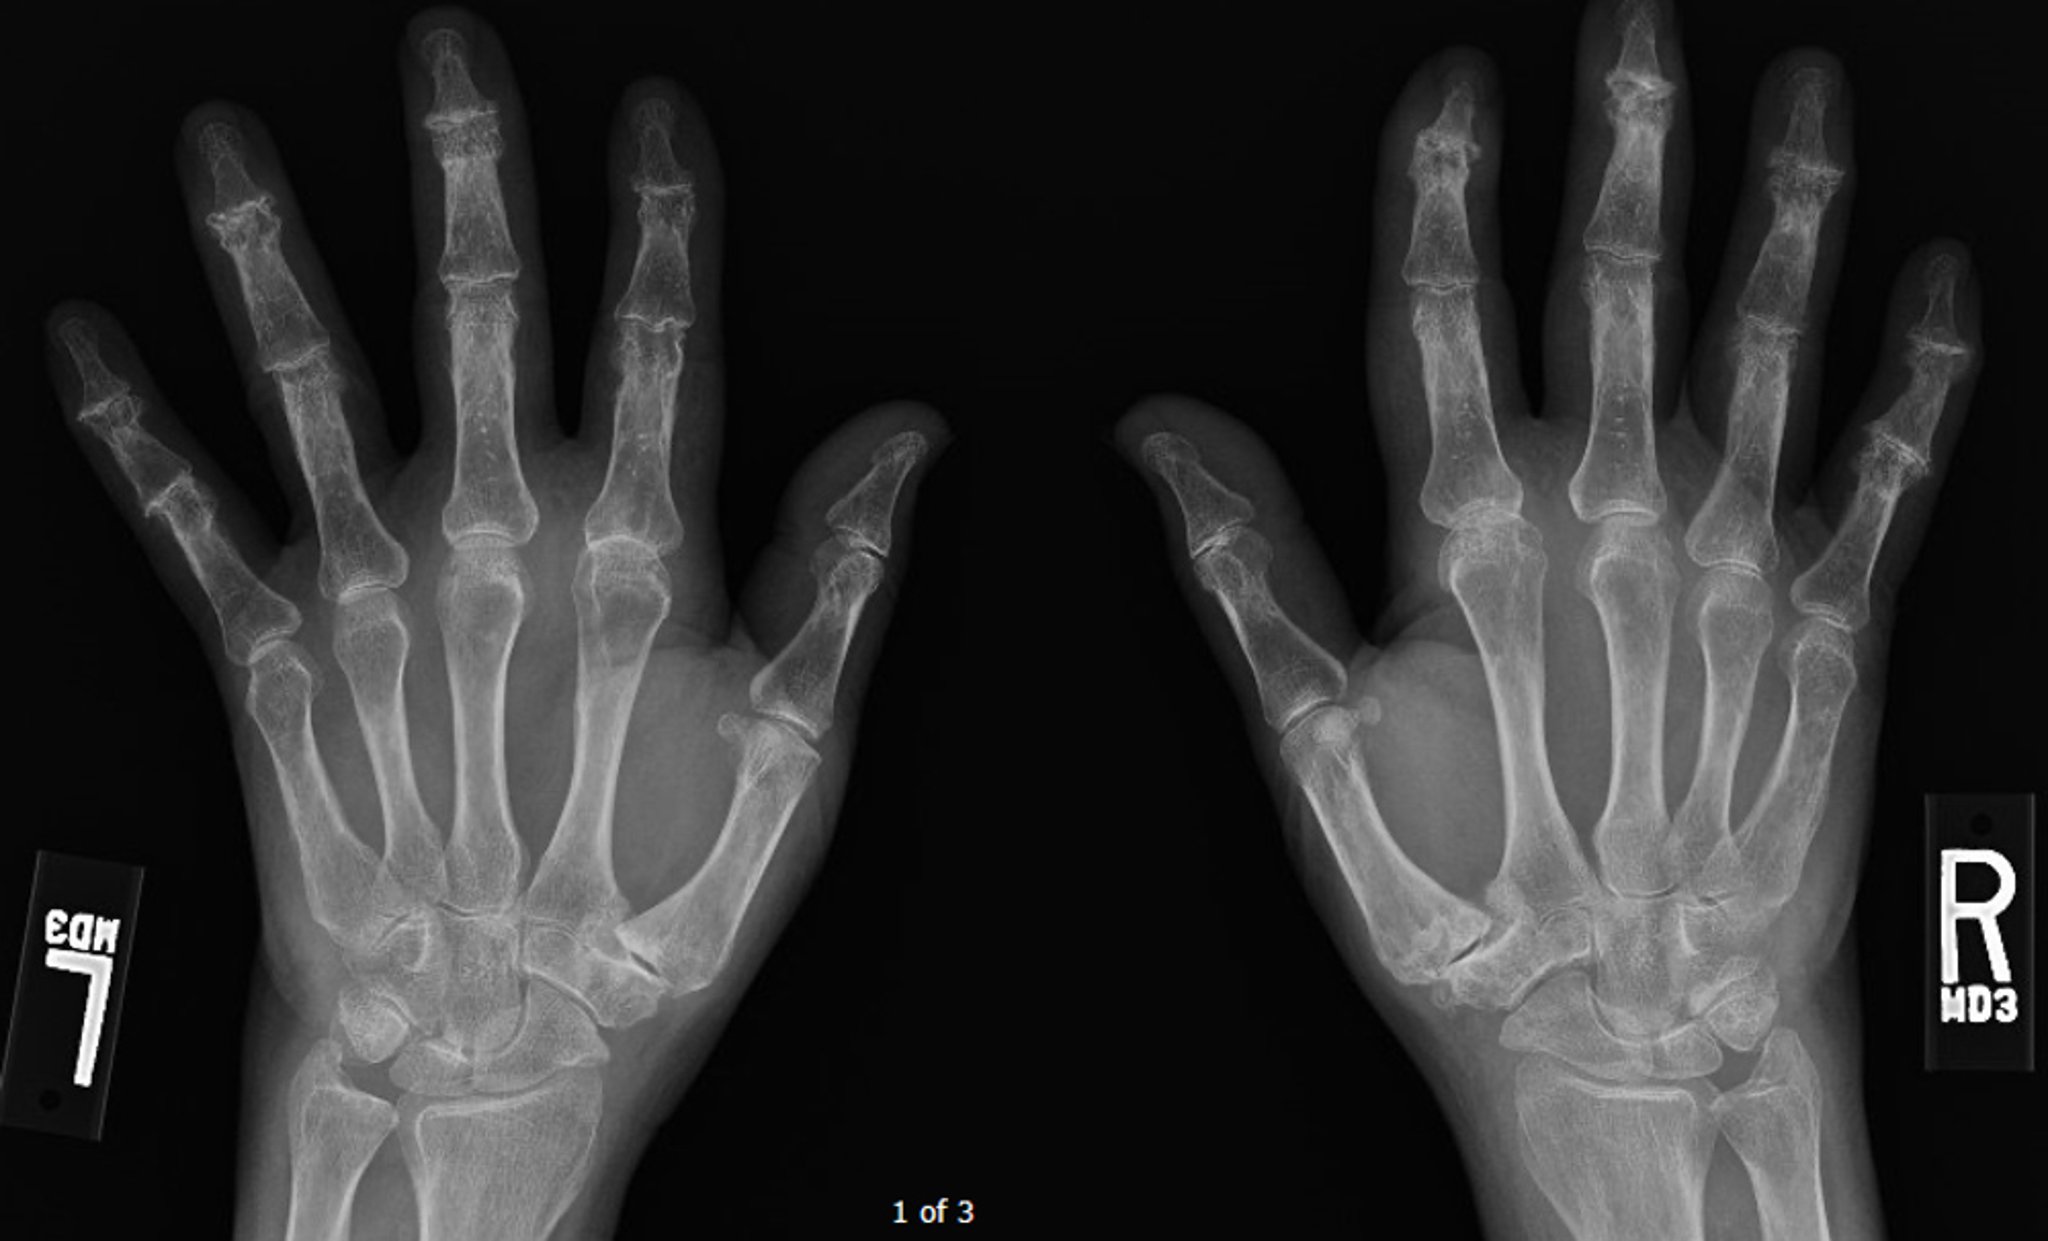

Эрозивный остеоартрит

Эта рентгенограмма показывает прогрессирующий диффузный остеоартрит, наиболее выраженный в дистальных межфаланговых суставах, где можно увидеть несколько центральных эрозий.

Image courtesy of Kinanah Yaseen, MD.